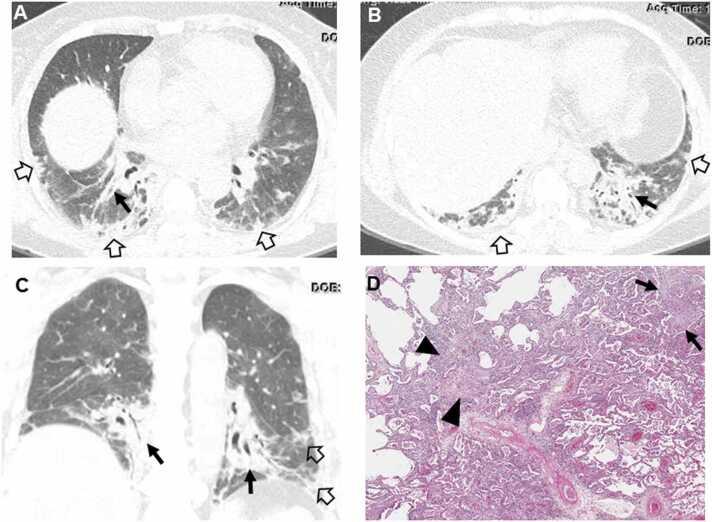

Connective tissue diseases (CTDs) demonstrating features of interstitial lung disease (ILD) include systemic lupus erythematosus (SLE), rheumatoid arthritis (RA), systemic sclerosis (SSc), dermatomyositis (DM) and polymyositis (PM), ankylosing spondylitis (AS), Sjogren syndrome (SS), and mixed connective tissue disease (MCTD). On histopathology of lung biopsy in CTD-related ILDs (CTD-ILDs), multi-compartment involvement is an important clue, and when present, should bring CTD to the top of the list of etiologic differential diagnoses. Diverse histologic patterns including nonspecific interstitial pneumonia (NSIP), usual interstitial pneumonia (UIP), organizing pneumonia, apical fibrosis, diffuse alveolar damage, and lymphoid interstitial pneumonia can be seen on histology in patients with CTD-ILDs. Although proportions of ILDs vary, the NSIP pattern accounts for a large proportion, especially in SSc, DM and/or PM and MCTD, followed by the UIP pattern. In RA patients, interstitial lung abnormality (ILA) is reported to occur in approximately 20-60% of individuals of which 35-45% will have progression of the CT abnormality. Subpleural distribution and greater baseline ILA involvement are risk factors associated with disease progression. Asymptomatic CTD-ILDs or ILA patients with normal lung function and without evidence of disease progression can be followed without treatment. Immunosuppressive or antifibrotic agents for symptomatic and/or fibrosing CTD-ILDs can be used in patients who require treatment.

表现为间质性肺疾病(ILD)特征的结缔组织病(CTD)包括系统性红斑狼疮(SLE)、类风湿关节炎(RA)、系统性硬化症(SSc)、皮肌炎(DM)和多发性肌炎(PM)、强直性脊柱炎(AS)、干燥综合征(SS)以及混合性结缔组织病(MCTD)。在CTD相关ILD(CTD-ILD)的肺活检组织病理学检查中,多部位受累是一个重要线索,若出现这种情况,应将CTD列为病因鉴别诊断的首要考虑。CTD-ILD患者的组织学检查可见多种组织学模式,包括非特异性间质性肺炎(NSIP)、寻常型间质性肺炎(UIP)、机化性肺炎、肺尖纤维化、弥漫性肺泡损伤和淋巴细胞间质性肺炎。尽管ILD的比例各不相同,但NSIP模式占很大比例,尤其是在SSc、DM和/或PM以及MCTD中,其次是UIP模式。据报道,RA患者中约20%-60%会出现间质性肺异常(ILA),其中35%-45%的患者CT异常会进展。胸膜下分布以及基线时ILA受累程度较高是与疾病进展相关的危险因素。无症状的CTD-ILD或ILA且肺功能正常且无疾病进展证据的患者可以不进行治疗而进行随访。有症状的和/或纤维化的CTD-ILD患者若需要治疗,可使用免疫抑制剂或抗纤维化药物。